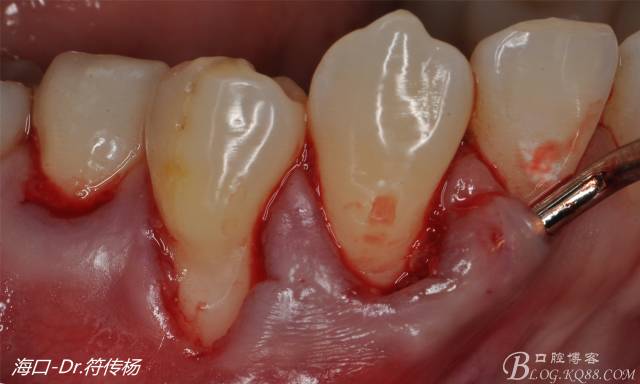

從病例圖片我們可以看到44牙頰側(cè)牙齦出現(xiàn)明顯萎縮

術(shù)前評(píng)估:退縮的齦緣在MGJ冠方 近遠(yuǎn)中牙槽嵴頂高度正常 屬于Miller -Ι類牙齦退縮 所有術(shù)后可以完全覆蓋

首先用顯微手術(shù)刀切斷手術(shù)范圍內(nèi)的牙周韌帶

然后使用下頜開隧刀剝離牙齦

最后使用牙齦乳頭分離器分離牙齦乳頭